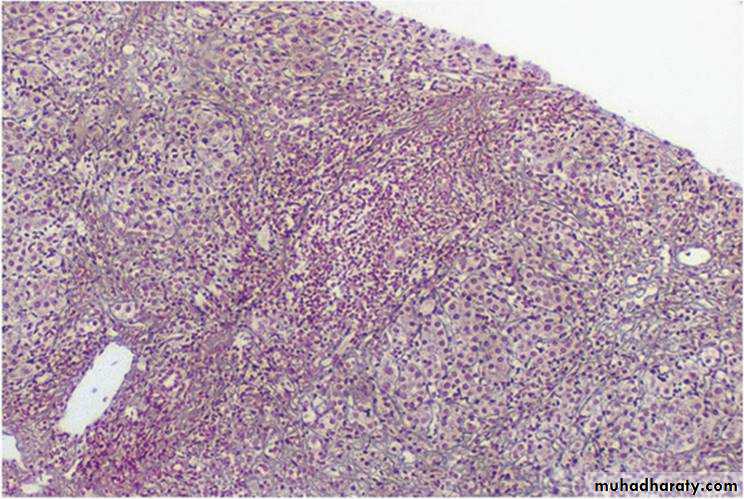

Hepatitis C virus infection with typical lymphoid aggregate formation in portal tracts

In chronic HCV infection, common findings are lymphoid aggregates and focal mild to moderate fatty change of liver.

chronic hepatitis, portal tract inflammation appears, but the lobular changes persist. There continues to be lobular disarray, However, despite the presence of portal inflammation, there is no significant bile duct infiltration or damage(arrow).